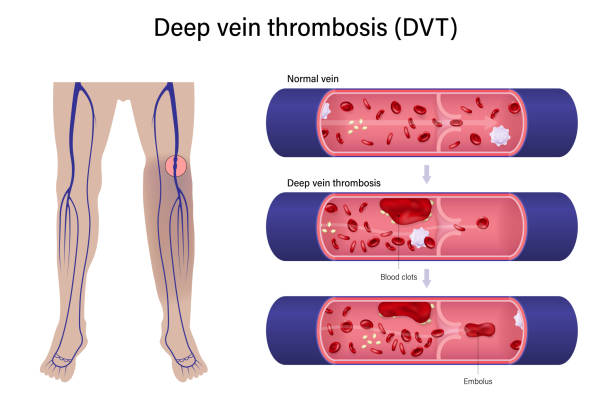

深部静脈血栓症 DVT の病態と予防見て!わかる!病態生理と看護 花子のまとめノート。

正常な血管と血栓ができた血管 イラスト素材5358451- フォトライブラリ。

深部静脈血栓症 - 血栓のベクターアート素材や画像を多数ご用意 - 血栓, 肺塞栓症, イラストレーション - iStock。

深部静脈血栓症、血栓症。塞栓。正常静脈と静脈瘤の構造。イラストは私が作成しました写真素材1443942500Shutterstock。

血栓ができている血管 イラスト素材6665451- フォトライブラリ。

3dイラストで表現された塞栓症と深部静脈血栓症の視覚的描写 写真背景 無料ダウンロードのための画像 - Pngtree。